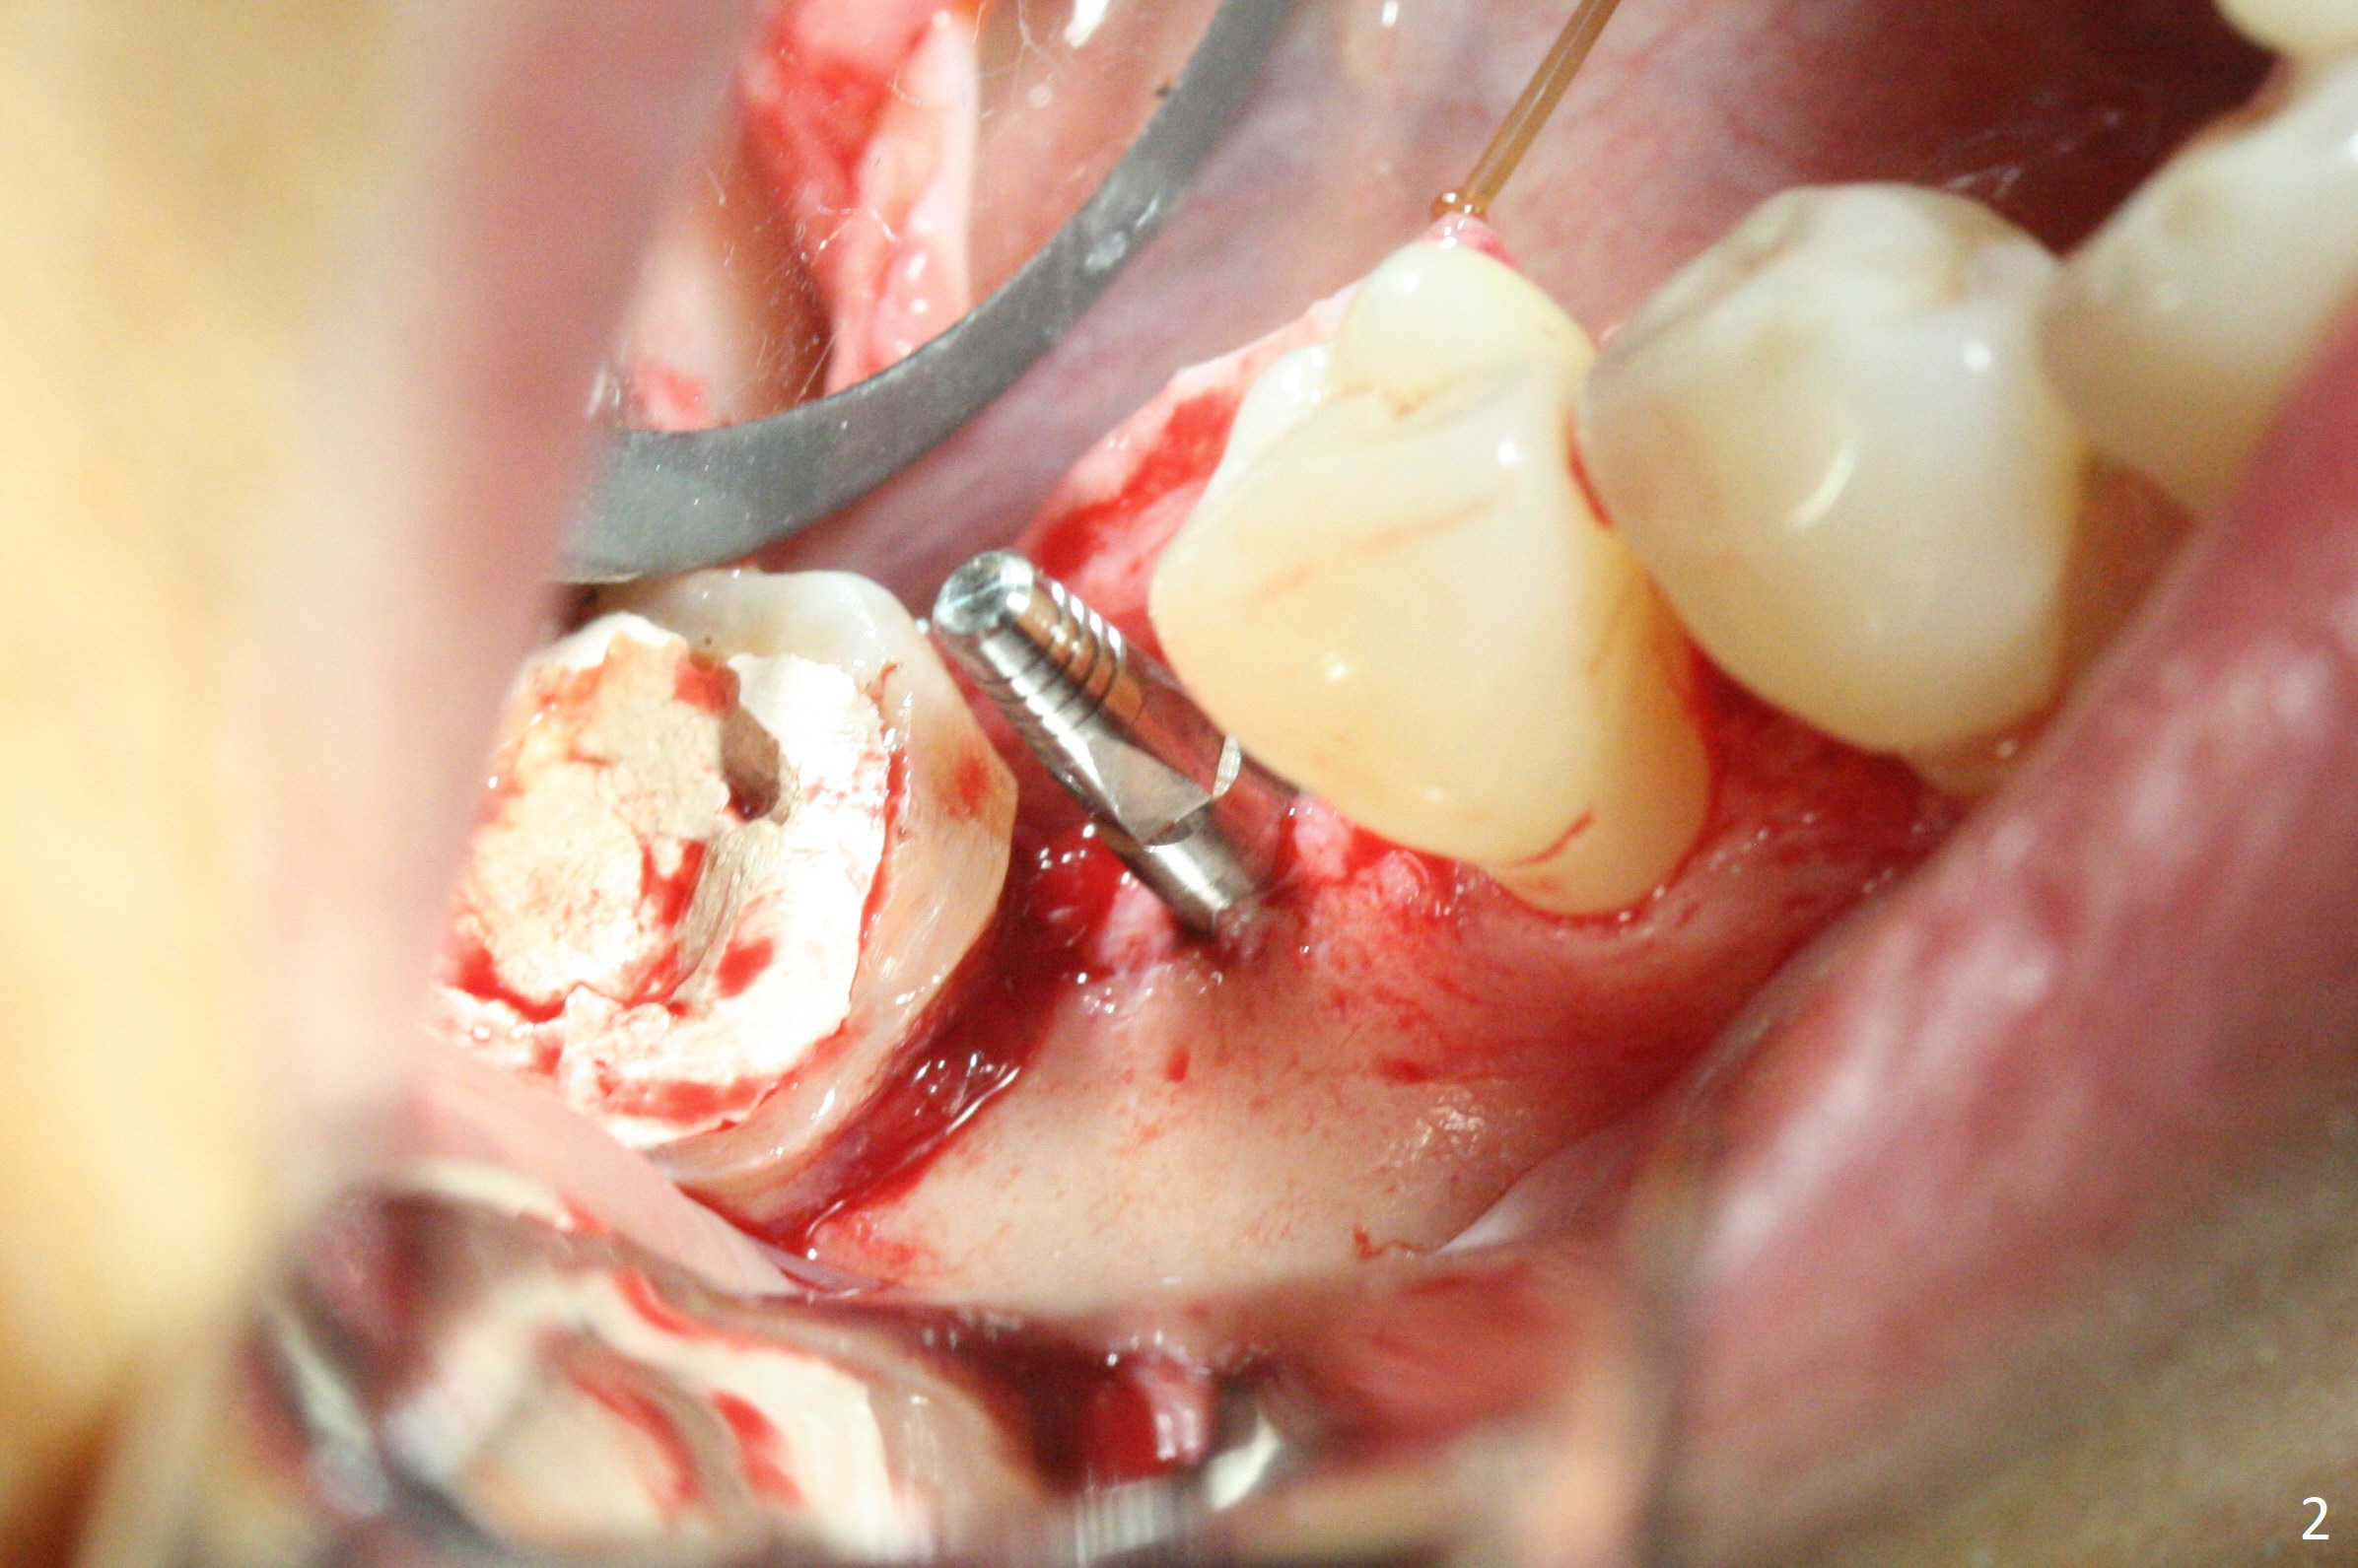

When a 1.2x12 mm drill is placed at #30, it passes the bone cavitation (Fig.1 red dashed line (low density)) twice for two-pointed fixation. So does the 3x12(2) mm 1-piece implant (Fig.2,3). The mesial margin of the tooth #31 is further reduced prior to suturing and periodontal dressing. Impression is taken 5 months postop (Fig.4). Residual cement mesial to the crown at #31 is later removed (Fig.5). Since the crowns were made at #30 and 31 at the same time, there appears no food impaction in between (Fig.6, 5.5 months post cementation).